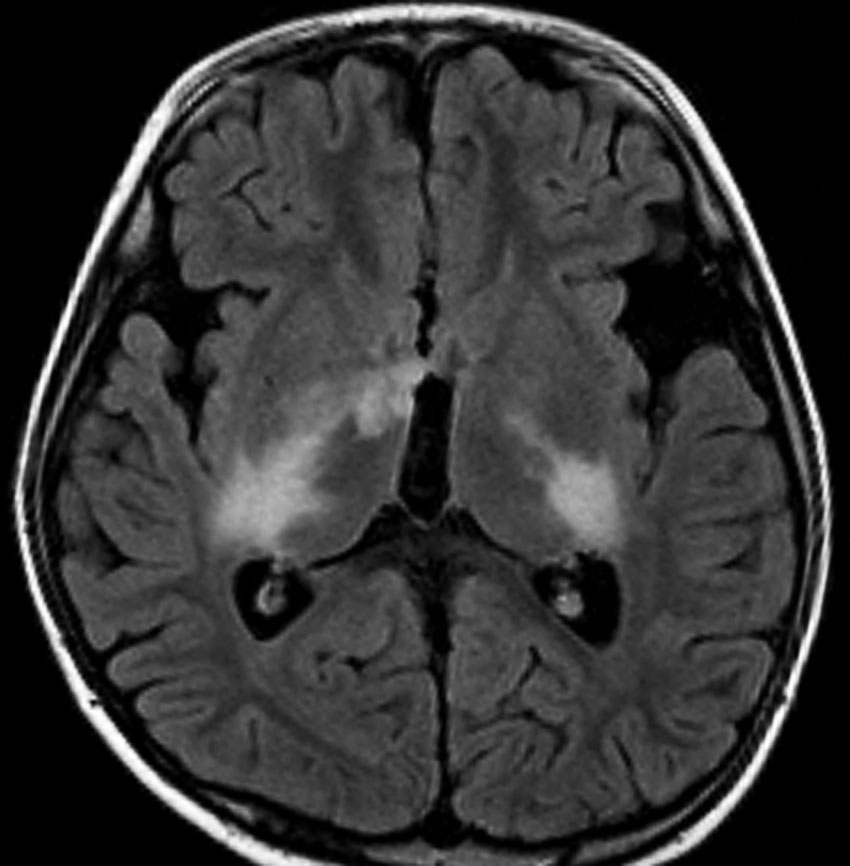

化学療法が有効なのは,上の画像のようにガドリニウム増強で強く増強されるタイプです,またT2強調画像で強い高信号になるものほど化学療法が有効です,要するに毛様粘液性星細胞腫の要素に化学療法が有効であるということです

この毛様細胞性星細胞腫はガドリニウムでほとんど増強されません(右側のMRI)から,化学療法を行っても小さくなりませんので,手術摘出する必要があります,実際に視床下部から発生したもの視交叉が犯されておらず,手術亜全摘出できました